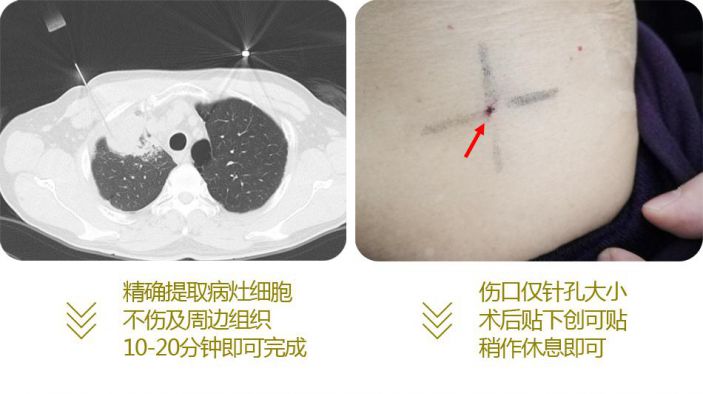

由于周圍型肺癌分型不同,治療方案不同。以往醫學界隻能在患者術後取腫瘤組織送病理檢查,才能确診其良惡性以及對腫瘤分型,即是先手術後确診。而經皮肺穿刺活檢術把診斷提到了前面,即先确診後治療,對周圍型肺腫瘤的診療無疑有重大意義。

由于周圍型肺癌分型不同,治療方案不同。以往醫學界隻能在患者術後取腫瘤組織送病理檢查,才能确診其良惡性以及對腫瘤分型,即是先手術後确診。而經皮肺穿刺活檢術把診斷提到了前面,即先确診後治療,對周圍型肺腫瘤的診療無疑有重大意義。